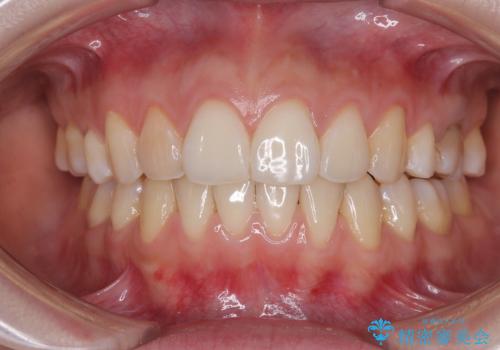

![[インビザラインモデレート] 抜歯矯正後の後戻り 出っ歯を治したいの症例 治療後](https://seimitsushinbi.jp/wp/wp-content/uploads/2025/05/P1463303-500x350.jpg?v=1746627320)

インビザライン・モデレートを用いて気になる後戻りを矯正治療

前歯のガタつきを改善 抜歯矯正後の後戻り